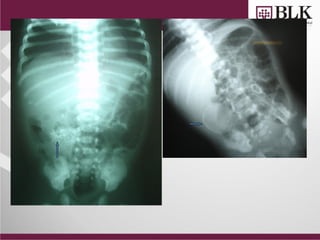

• Abdominal distension

from birth

• Antenatal scan: Echogenic

and dilated bowel

• X-ray

Abdominal distension since birth

 Meconium ileus

 Meconium peritonitis/ascites

 Abdominal lump

 Ascites

Meconium Ileus

• Gastrograffin enema

Exploration

CASE

 Term male Newborn

 Antenatal scan s/o

echogenic bowel

 Bilious aspirates &

not passed meconium

 Abdominal distension

since birth

Meconium Peritonitis